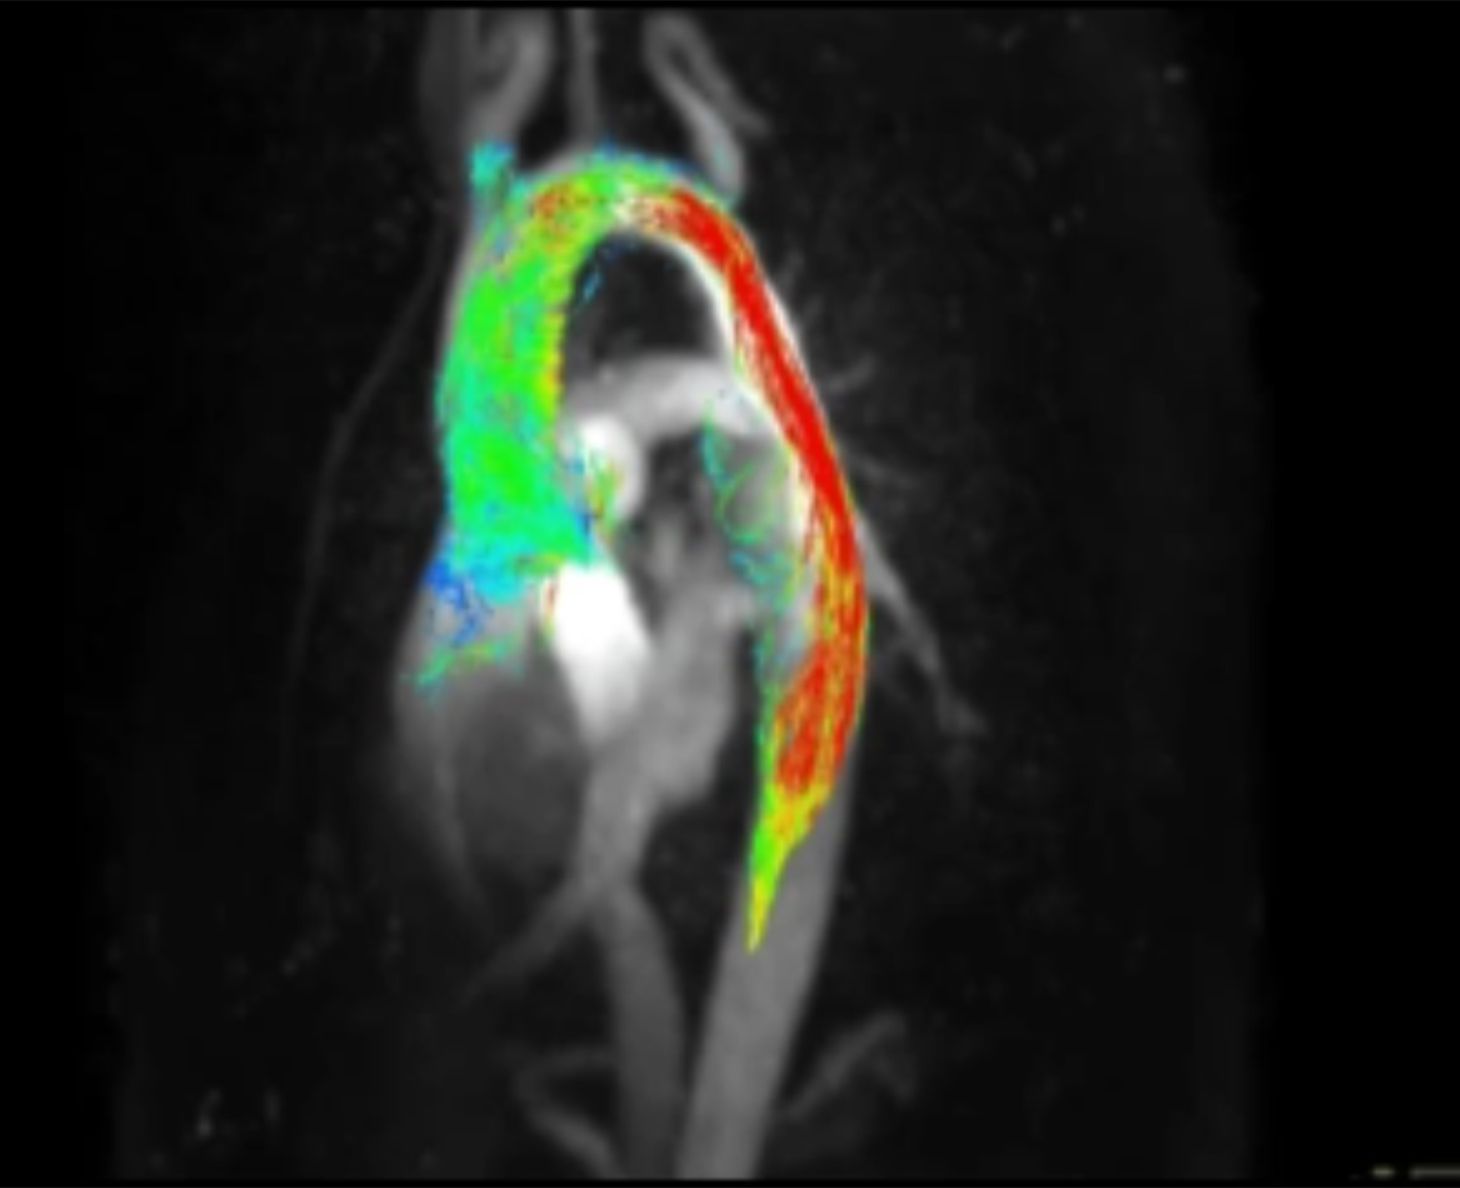

4-dimensionale Flussmessungen, die den Blutfluss neben einer 3-dimensional-räumlichen Aufnahme zusätzlich über die Zeit (4. Dimension) darstellen. Turbulente Strömungen und weitere physikalische Berechnungen können mit dieser modernen Forschungssequenz erfolgen.